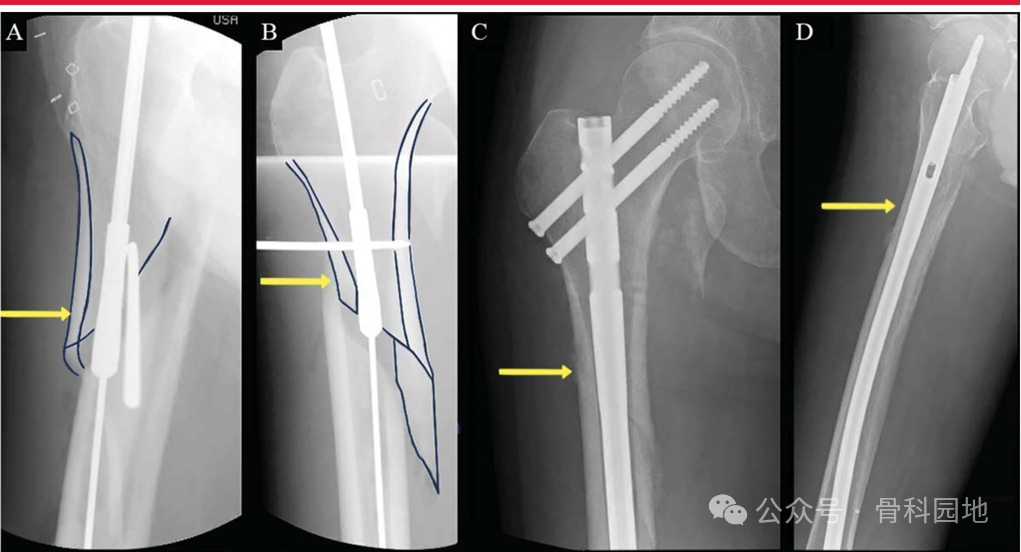

适当的进针点和适度的扩髓可以矫正成角畸形。进针点偏外导致内翻复位不良,在需要扩髓的髓内钉,转子下区与股骨近段相连的部分,如果扩髓不充分,可作为一种变形力(如下图)。外侧皮质会导致内翻畸形,内侧皮质则会导致外翻畸形。

四、阻挡钉辅助复位

髓内钉内固定是一种安全有效的复位方法。阻挡钉可以用螺针、钻头或克氏针来完成。我们提倡使用阻塞针而不是螺钉或钻头,因为能够很容易地作出纠正。在常见的骨折类型中,股骨近端有完整的外侧和前皮质。两根阻挡钉,一根内侧一根后侧,此外,阻断针可作为一种操纵杆,辅助维持复位。